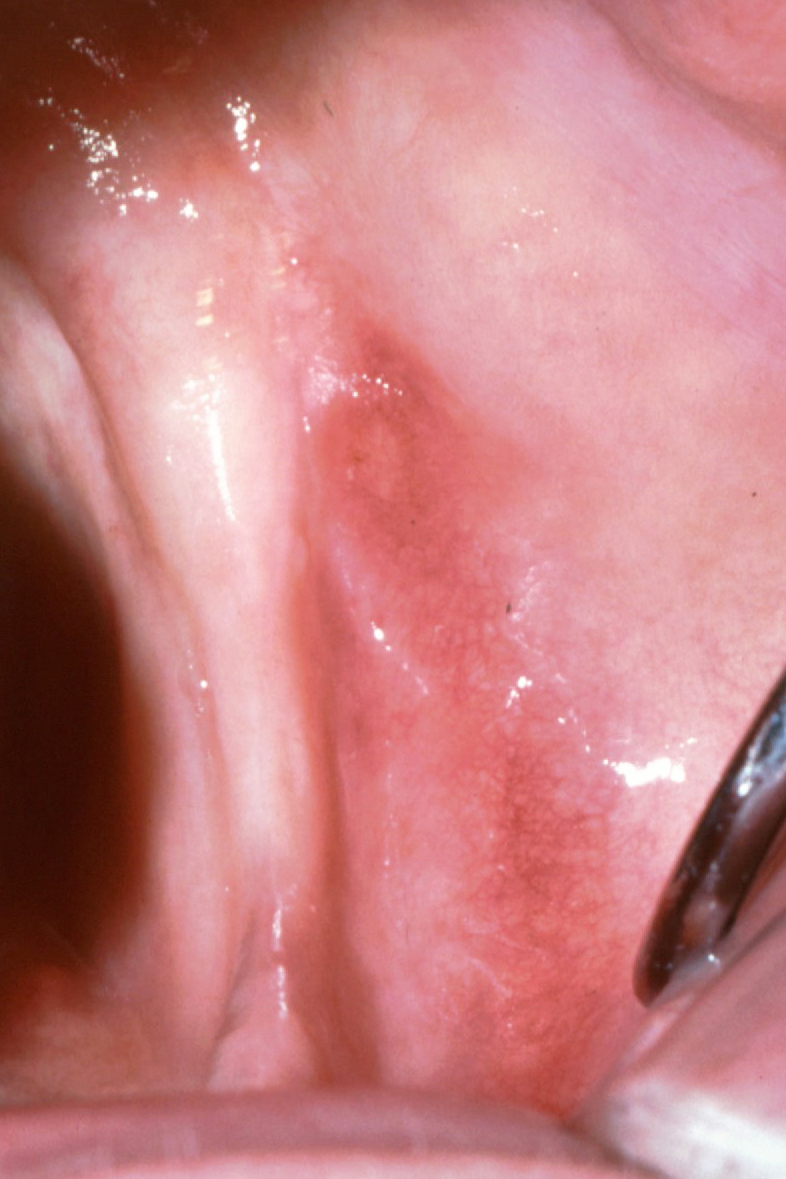

The buccal shelf presents a loosely attached mucosa,6,16 whereas the crest of the ridge usually consists of a firmly attached mucosa unless the ridge demonstrates an excessive resorptive pattern (Figure 1). The buccal shelf, meanwhile, presents a thick cortical bone and is part of the basal bone receiving tensile stimulation through the actions of muscular attachments. The anatomy and trabecular patterns also are structured to resist the forces of mastication better than the crest of ridge, although the mucosa is less keratinized and prone to displacement under pressure.5,6

Fig 1. Mandibular edentulous arch demonstrating buccal shelf lateral to ridge crest.

Figure 1